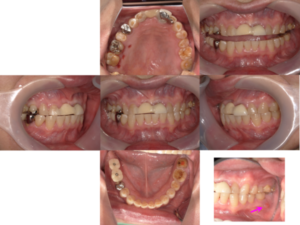

では、初診時の口腔内写真とレントゲン写真です。

初診時

矯正的圧下は模型上でシミュレーションを行ってから行いました。圧下の経過を示します。

治療中

矯正用のアンカースクリューを用いて右上の奥歯を圧下しました。

右上の奥歯を圧下した後の口腔内写真です。